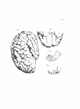

Gall, F. J. (1818). Anatomie et physiologie du système nerveux en général, et du cerveau en particulier, Avec des observations sur la possibilité de reconnoître plusieurs dispositions intellectuelles et morales de l´homme et des animaux, par la configuration de leurs têtes.

Librairie Grecque-Latine-Allemande, Vol. 3, I-XXXV u. 1-379 100 planches.